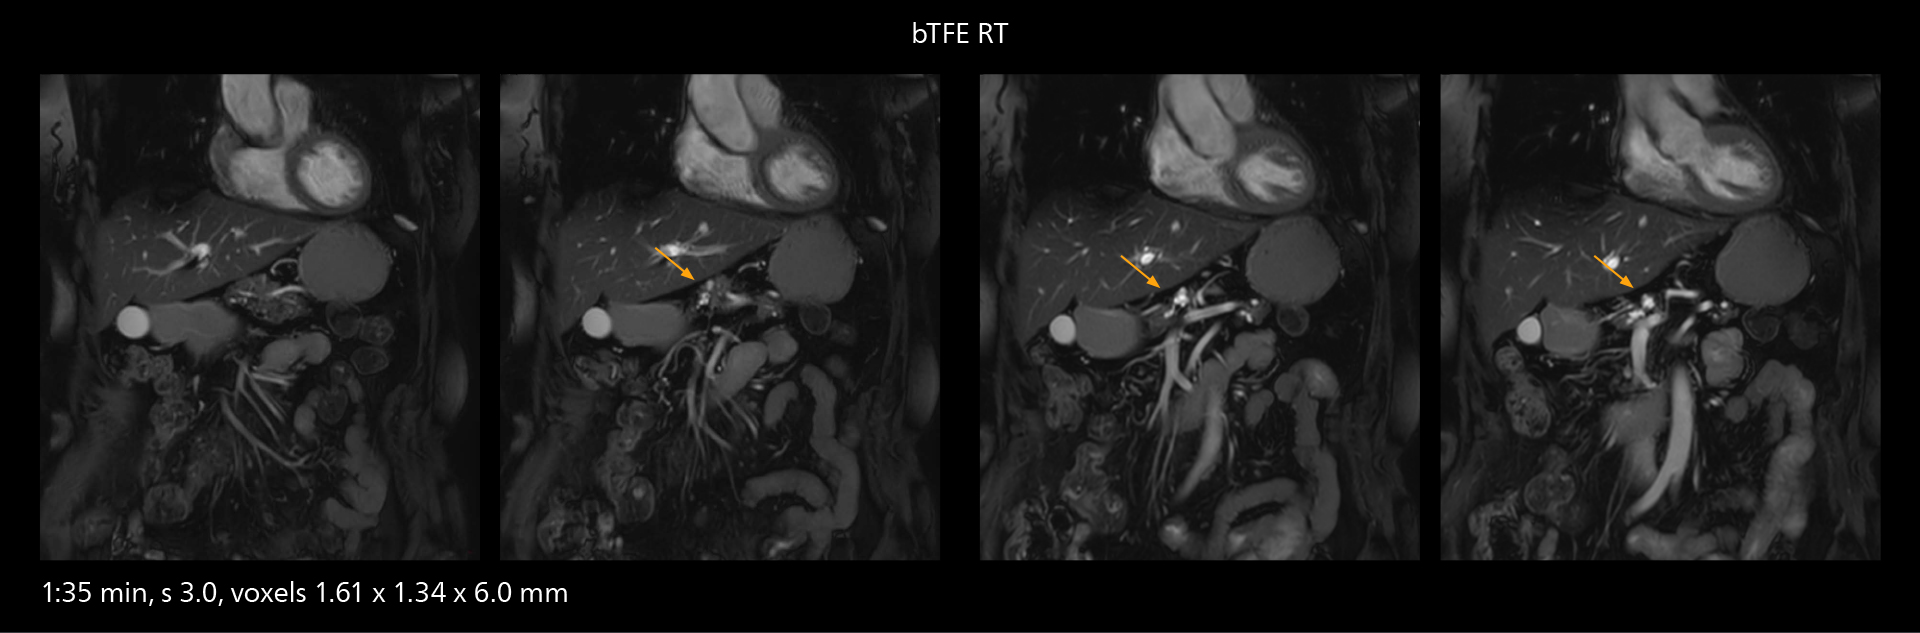

Diffusion studies benefit from powerful gradients

The high performance of the Vega HP gradients is particularly impressive in DWI. “The Vega HP gradients enable us to scan faster and use b-values as high as 2000, for example in prostate DWI and in DWIBS, which provides image quality that is remarkably improved over the previous system and we are able to more easily see lesions.”

The value of the Elition X gradients is also evident in DWIBS studies. “The fact that we can consistently obtain distortion‐free DWIBS while reducing imaging time at three coronal stations is excellent,” Dr. Makuuchi says. “In these patients, it’s also important that the application of Compressed SENSE to T2‐weighted, STIR and mDIXON sequences has no impact on the examination time of whole‐body imaging. As a result of the increased speed and higher image quality we realize, DWIBS studies have now become routine examinations.”